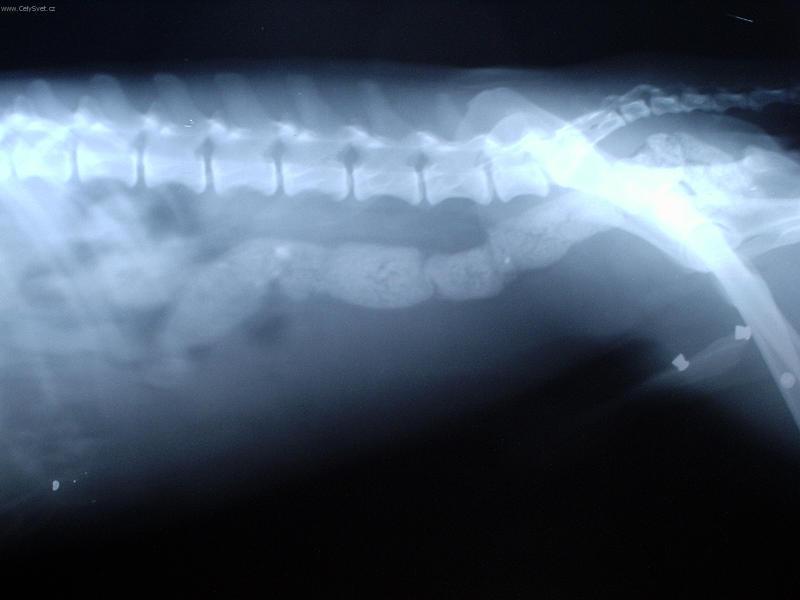

Foto galerie (fotky, obrazky): Cizí tělesa v zažívacím traktu a kostní trus.

Clanek: Cizí tělesa v zažívacím traktu a kostní trus.

Fotky: Cizí tělesa v zažívacím traktu a kostní trus. (foto, obrazky)